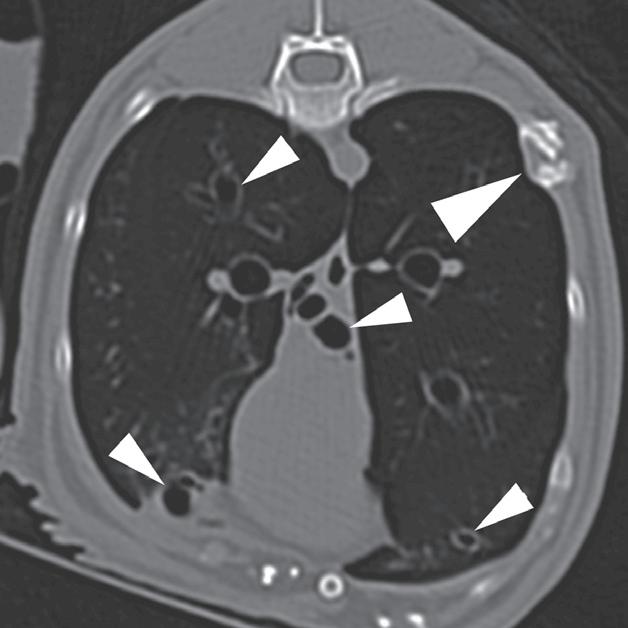

Rycina 4.6.4. Kardiogenny obrzęk płucny (kot) TK

Badanie wykonano u 4-letniej, kastrowanej samicy kota domowego krótkowłosego dializowanej z powodu niewydolności nerek. U pacjentki obserwowano echokardiograficzne objawy łagodnej kardiomiopatii. W momencie wykonywania tomografii komputerowej kot był umiarkowanie przeciążony płynami. Obraz na ryc. a jest reprezentatywnym obrazem na poziomie tylnej części klatki piersiowej, a obrazy przedstawione na ryc. b i c stanowią powiększenie ryc. a. Niewielka objętość płynu opłucnowego unosi powietrzne płuco (a – czarna strzałka). Widoczny jest łagodny, rozproszony wzrost atenuacji płuc z dodatkowymi, licznymi zmianami w typie matowej szyby. Wydaje się, że te ostatnie nacieki są najbardziej widoczne wokół naczyń płucnych (a–c – białe strzałki). Badanie pośmiertne potwierdziło, że nacieki były spowodowane obrzękiem płuc. W tym przypadku obrzęk prawdopodobnie był wynikiem względnej niewydolności komór serca spowodowanej kardiomiopatią i przeciążeniem płynami